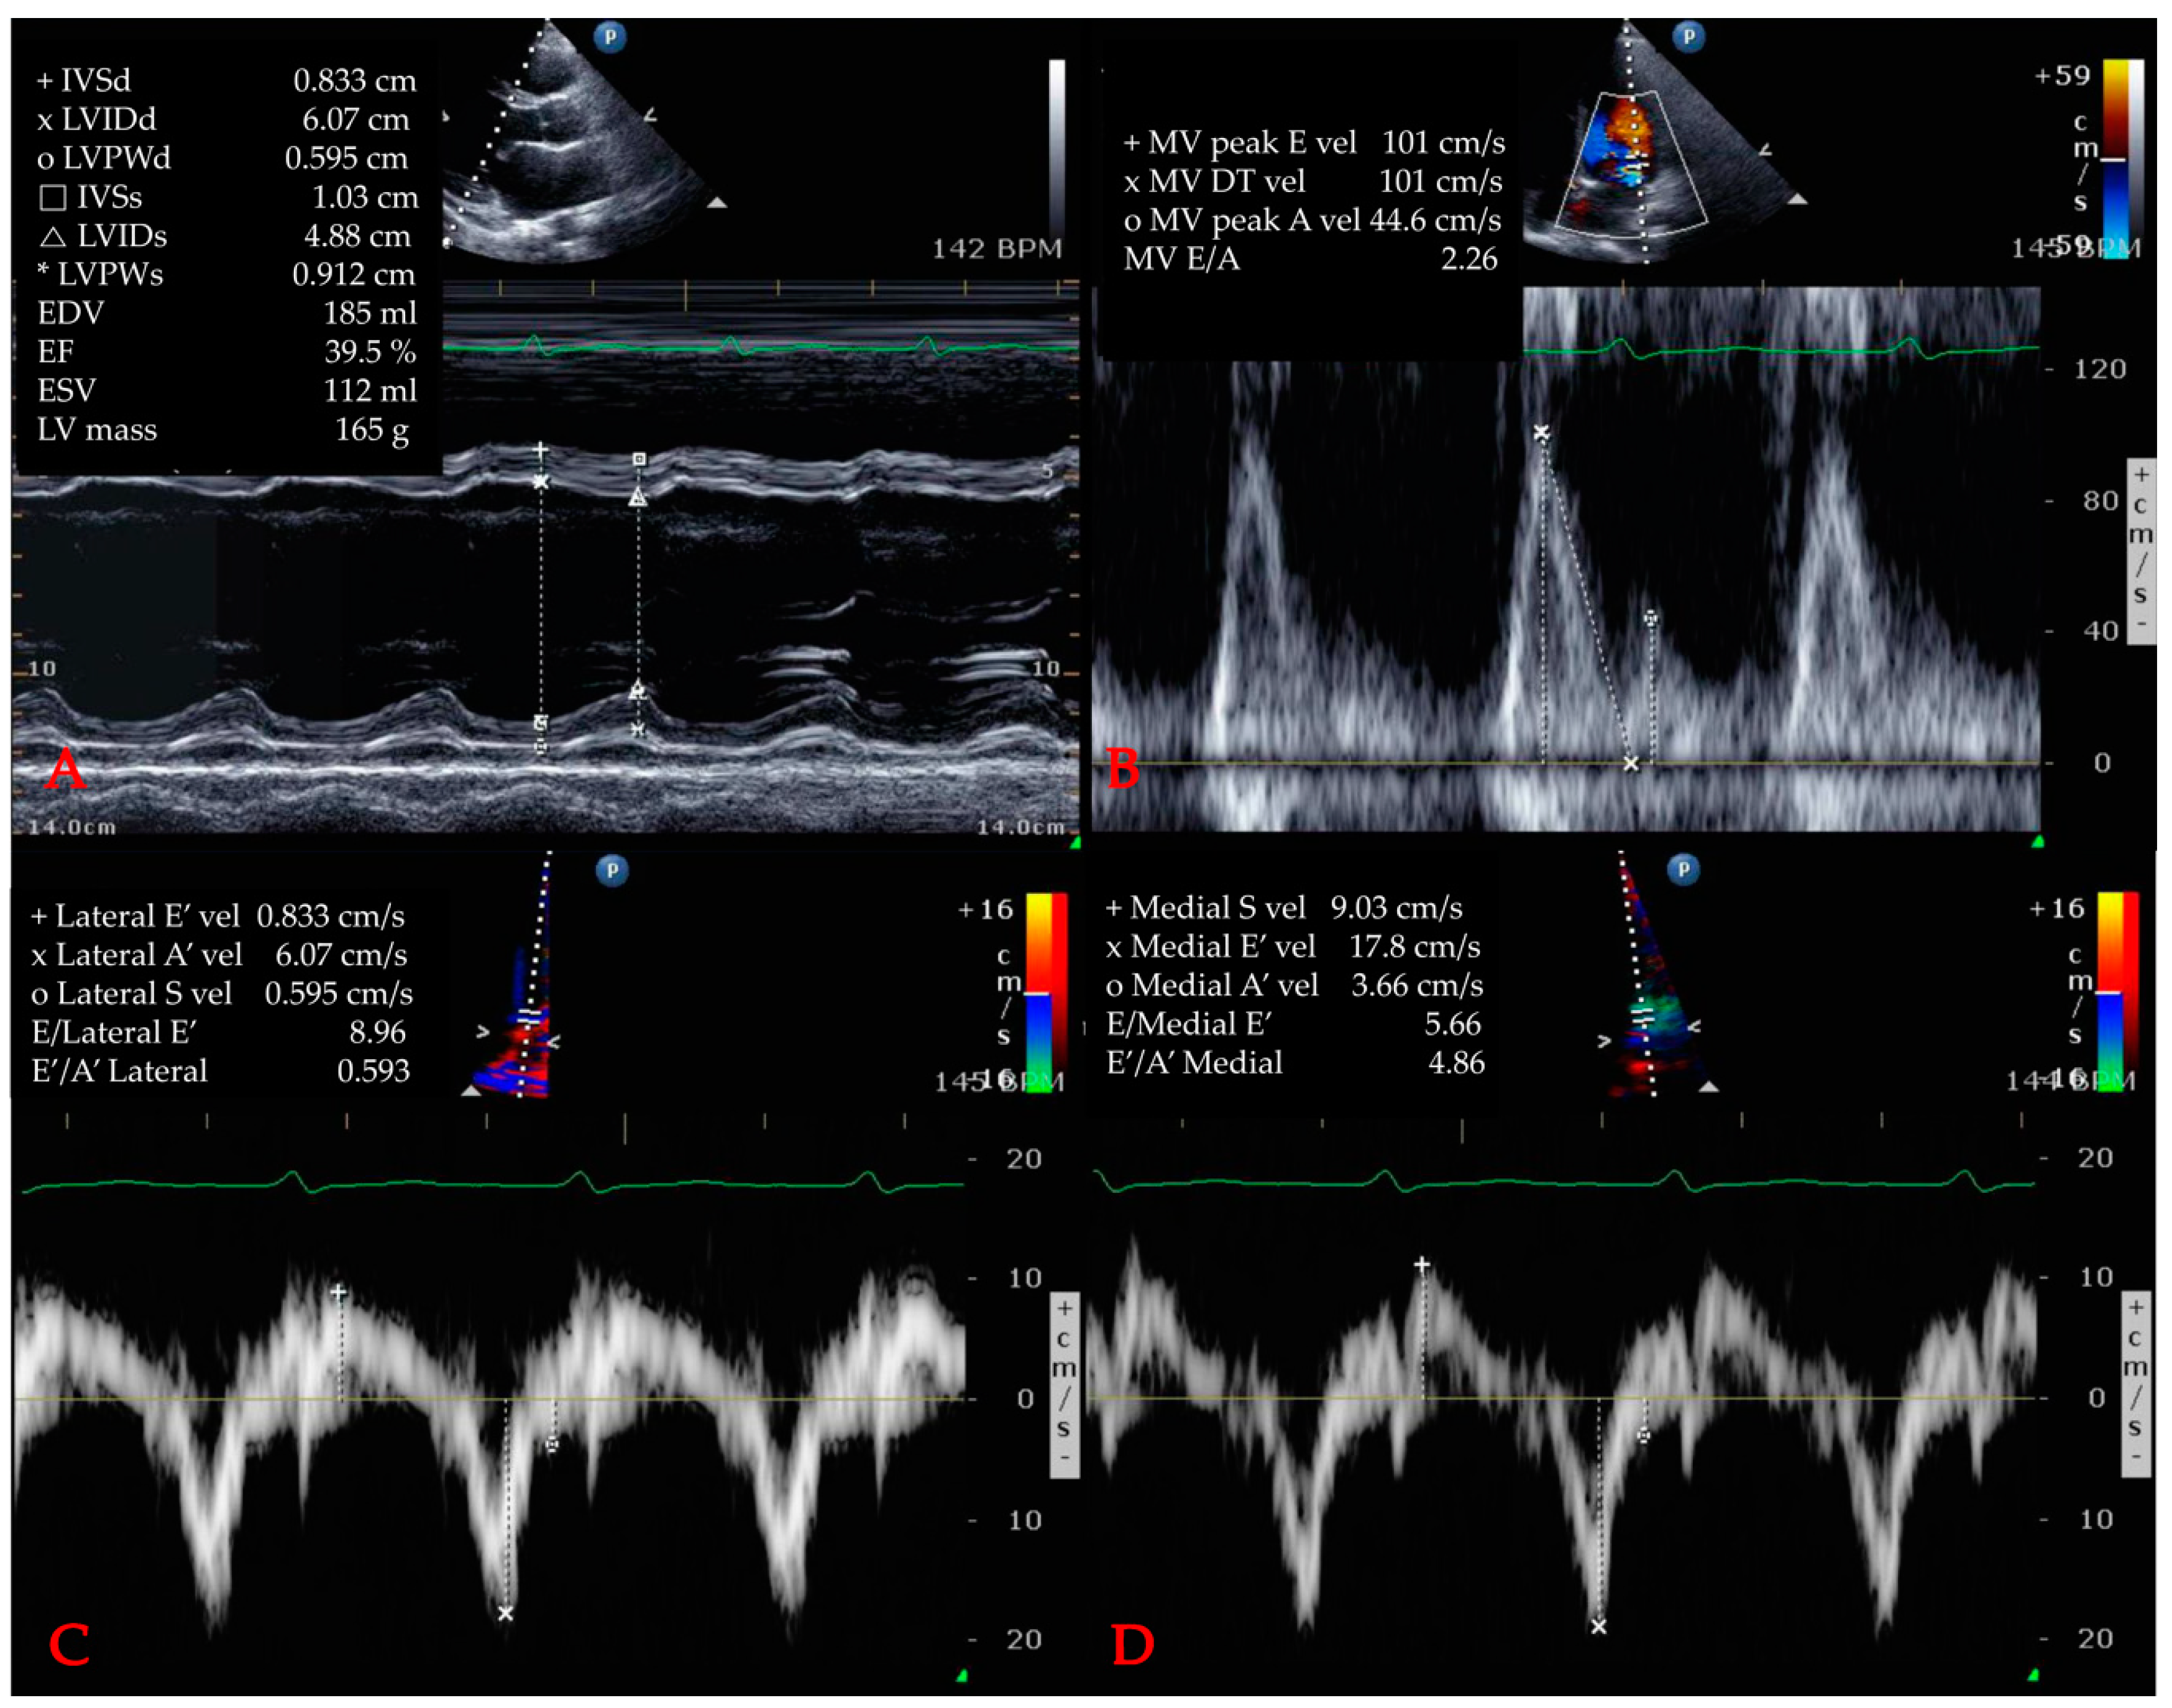

2.5. Echocardiographic Variables